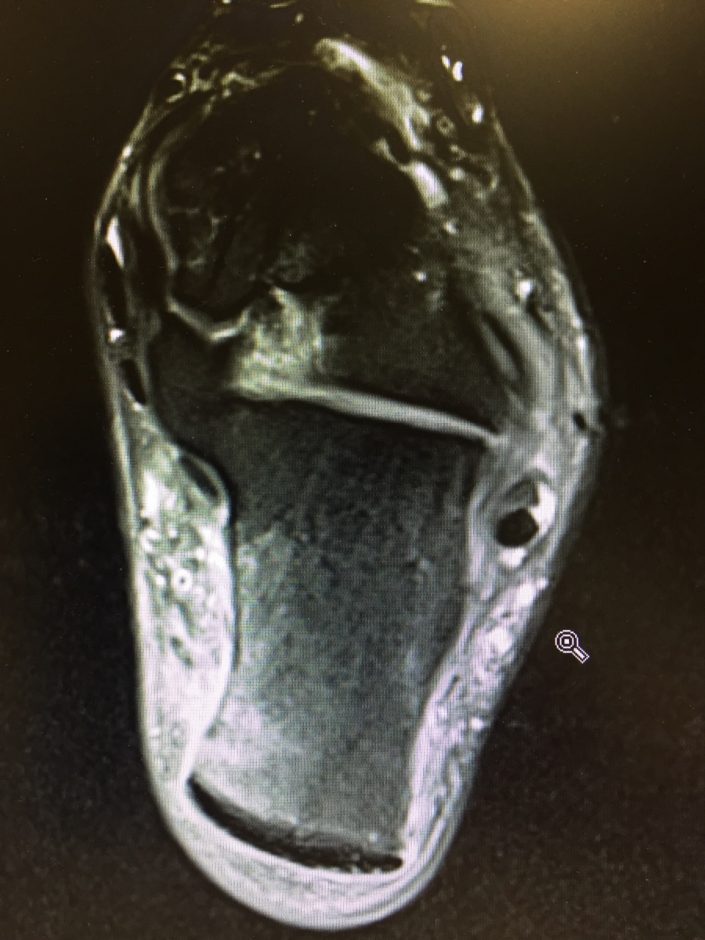

Loppuleirin suunnitelmat meni siis uusiksi. Kahden kisan sijasta uintia, spinningiä ja turisteilua. Yritin pitää kuitenkin mielen positiivisena 😉 Uskoin kuitenkin tässä vaiheessa vielä vahvasti, että ei tämä mikään pitkä juttu ole. Eihän oireita ollut tuntunut kuin muutaman päivän ajan. Menin tarkistuttamaan asian suhteellisen pian ortopedille ja siitä magneettikuvaan. Ja voi jehnat. Diagnoosiksi tuli rasitusosteopatia. Että sillä lailla. Ei siis vielä rasitusmurtuma, kuten otsikossa hieman virheellisesti kirjoitin, vaan rasitusmurtuman esiaste (termi rasitusosteopatia on ehkä hieman vieraampi, jonka vuoksi selkeytin otsikkoa). Käytännössä se tarkoittaa usean viikon taukoa juoksuista ja hypyistä.